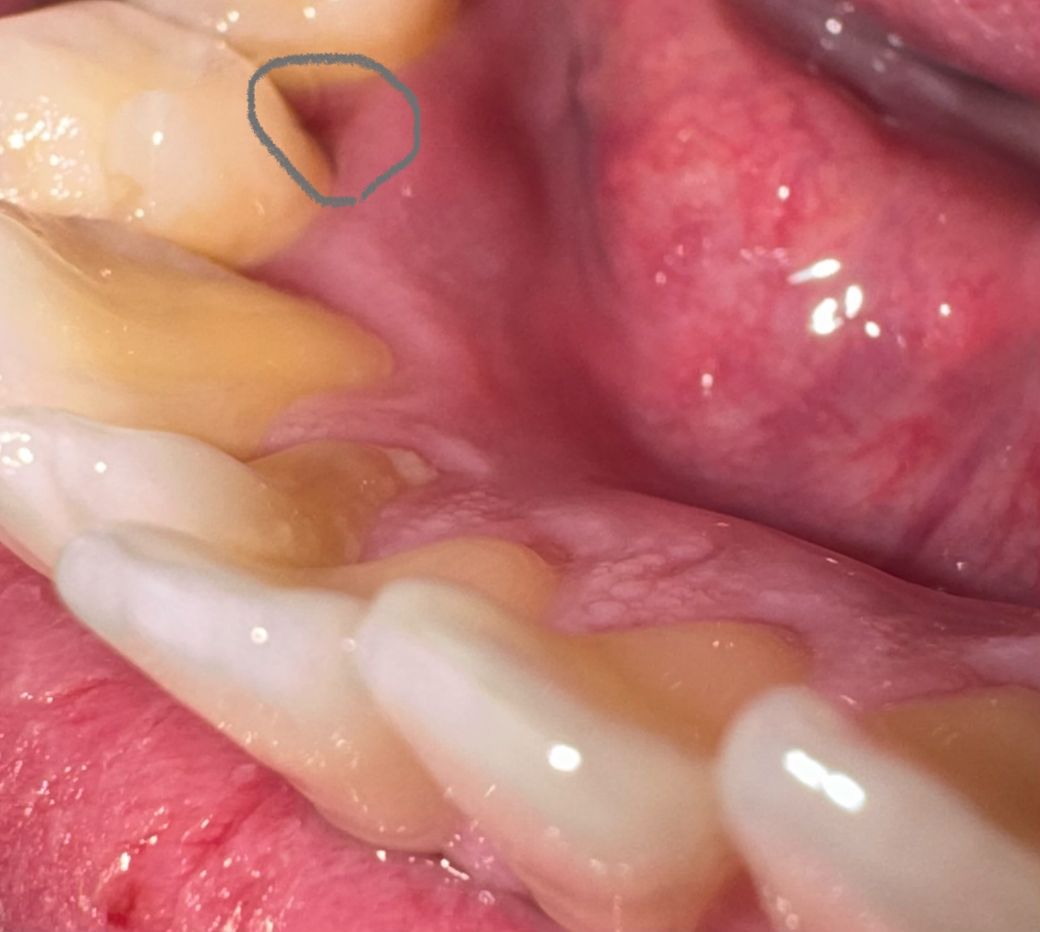

아래치아 안쪽 치간유두부위부분 파임 봐주세요

아래치아 안쪽 사진속 치간유두부위가 몇달전쯤

치실 사용하다가 피가나면서 치간유두부위가 손상된거같은데

손상되고 그부분 옆면 치아가 옆면 뿌리가 살짝보이면서

홈이(파여서) 생겨서 그 사이에 음식물이 잘 끼고 그래서

• 1번 째 사진